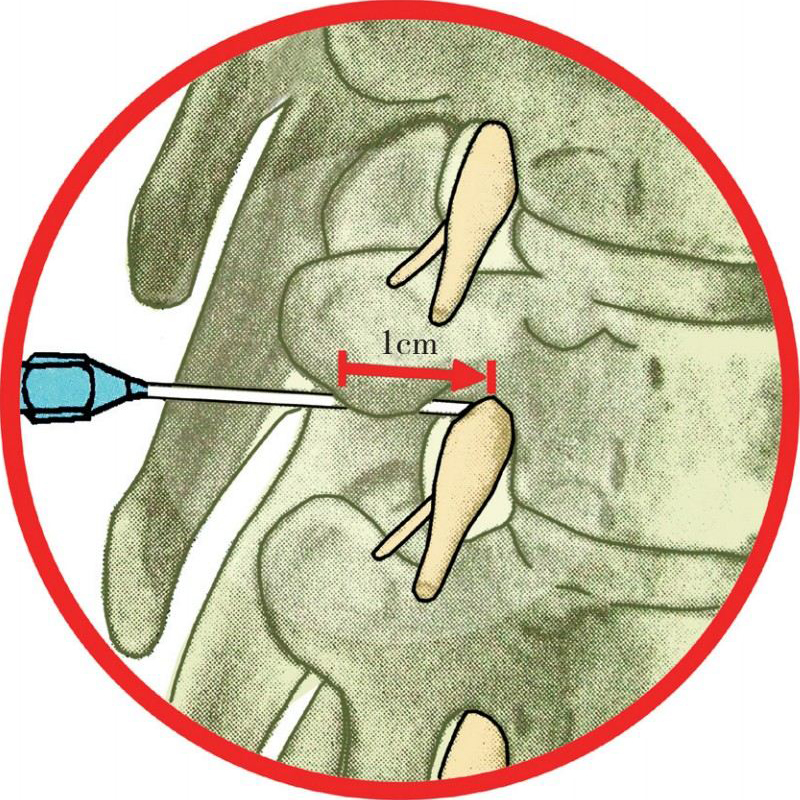

腰部脊神经腹支和背支在椎管内下行,在各自的椎间孔形成脊神经。椎间孔朝向侧方。椎间孔的顶部和底部由椎弓根构成。后外侧壁大部分由下面的上关节突,小部分由上面的下关节突及关节囊构成。前内侧壁由上面椎体的尾端和椎间盘的后外侧角构成(图4-48)。

图4-48 椎间孔穿刺术进针位置的解剖图

脊神经在硬膜袖中斜向穿出椎间孔。神经根在向外下穿过椎间孔时,分出腹支和背支。腹支经横突前方走行。根动脉是腹主动脉的分支,经椎间孔供应脊髓。对椎动脉的了解能帮助顺利进行椎间孔注射。

3.具体操作 在透视下标记出靶椎间孔的部位。进针点旁开棘突5~6cm,斜行向前向内,触及上关节突外侧部分后,改变方向再向深部刺入,感到阻力消失感后,即已进入椎间孔内(图4-49)。但不应过深进针,以免损伤神经根周围的血管组织或误入蛛网膜下腔。抽吸无回血及脑脊液后注入药液2~3ml,能产生整个神经根周围的阻滞作用。椎间孔穿刺注药法可以在C形臂机下应用(图4-50、图4-51),也可不在透视下应用。但其穿刺技术要求较高,必需经验丰富的医师操作。